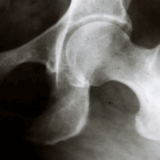

• また、Chang et al.(2016, Journal of Orthopaedic Research の研究では、股関節疾患患者では健常者に比べて深部感覚が有意に低下しており、それが動作時の筋活動パターンに影響することが示されています。